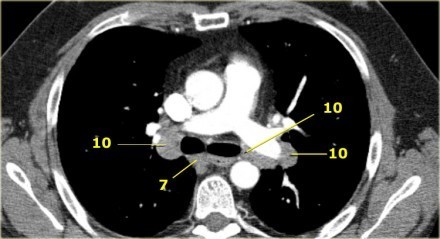

4R. Paratraqueais Inferiores Direitos

Limite superior: intersecção da margem caudal da veia inominada (brachiocefálica esquerda) com a traqueia.

Limite inferior: borda inferior da veia ázigo.

Linfonodos 4R estendem-se para a borda lateral esquerda da traqueia.

Linfonodos paratraqueais 4R